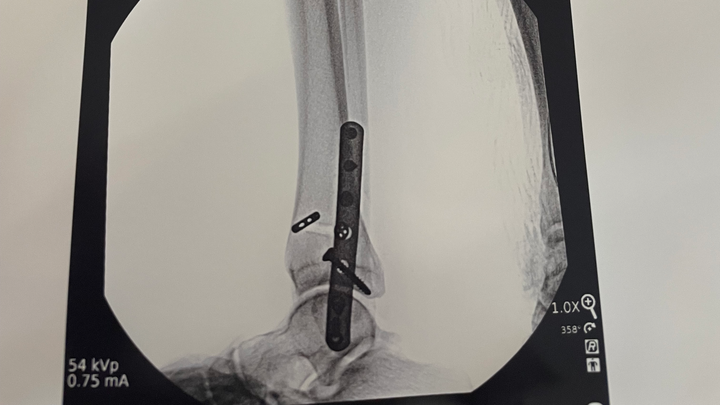

Hi, my name is Hannah Tompkins. On Saturday March 22nd I broke my ankle and on Monday March 25th I had surgery. I am currently non weight bearing, I am out of work for about a month so anything helps! I have bills to pay and groceries I need which is becoming difficult due to not being able to work. Again, anything helps and would be greatly appreciated!